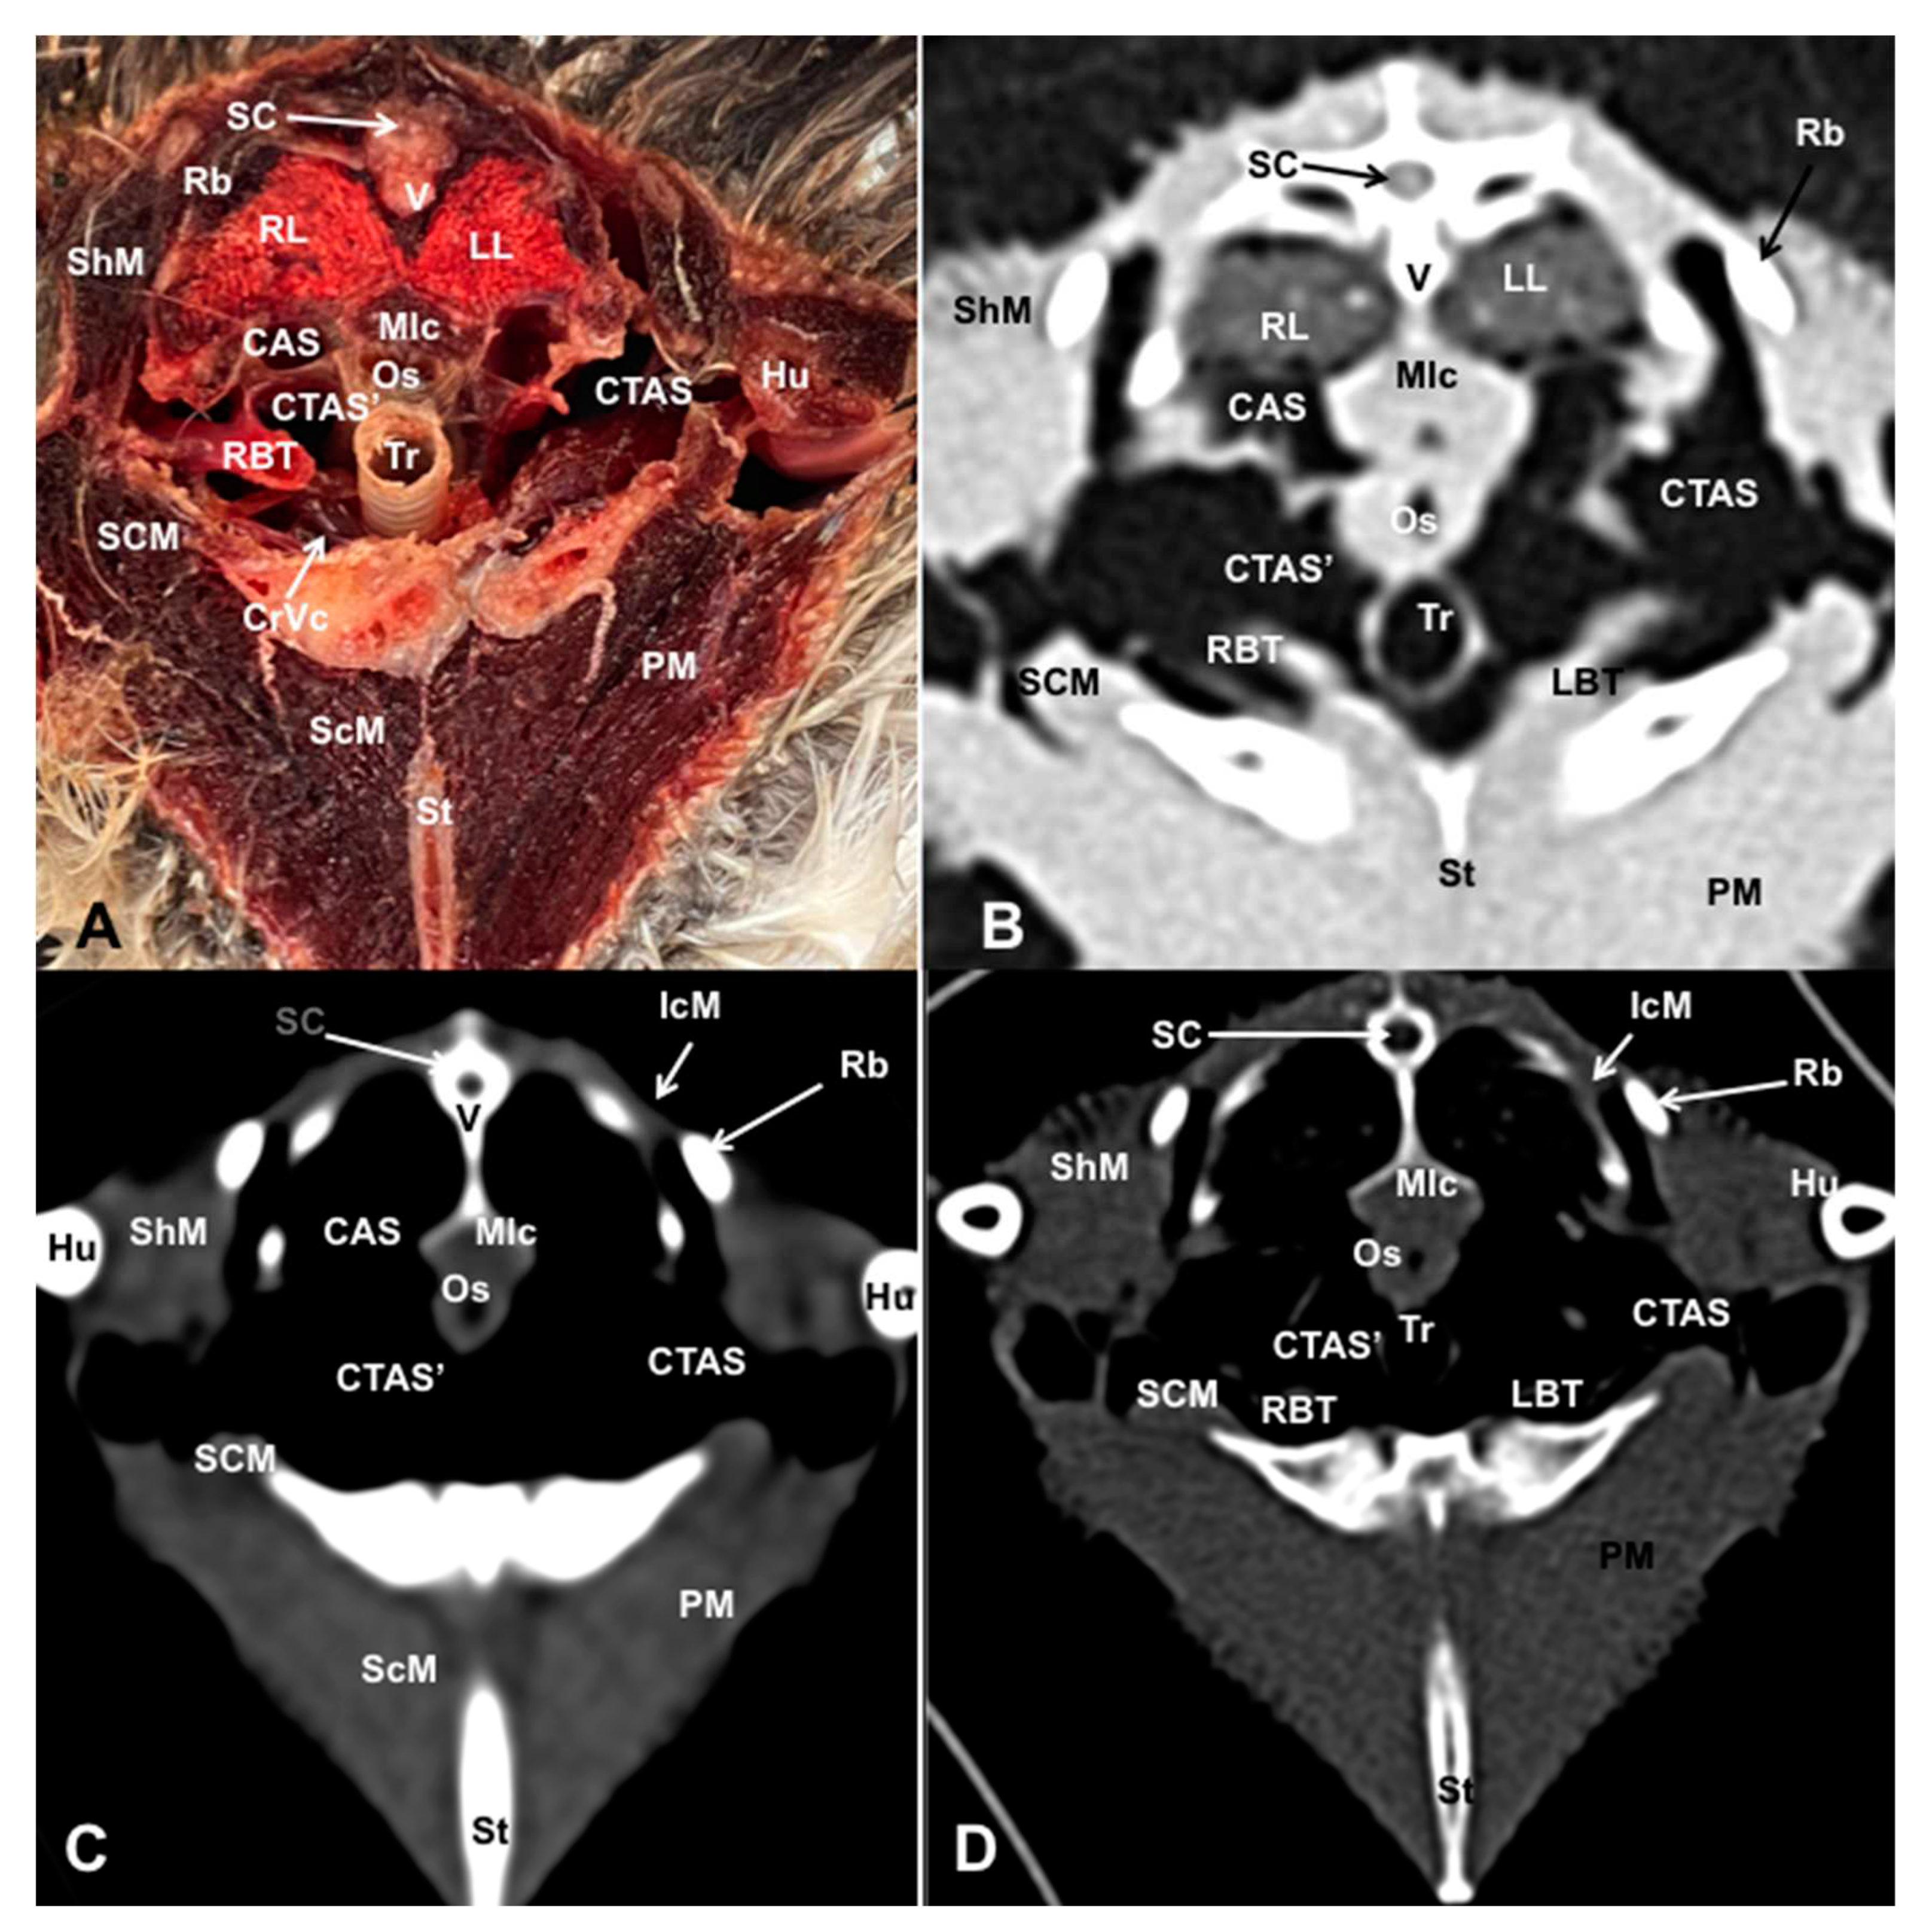

3.1. Anatomical Dissections and Cross-Sections

3.2. Computed Tomography Images